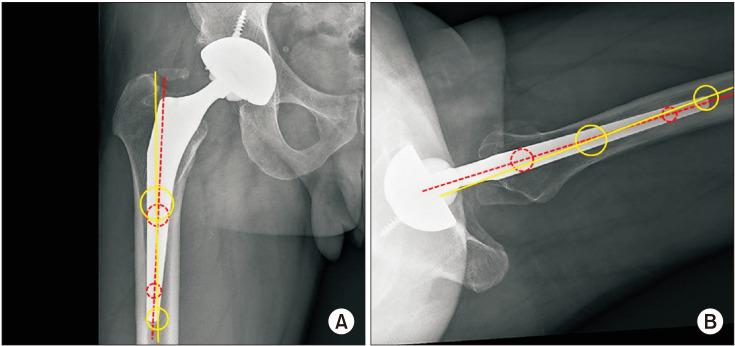

The current trend of using short femoral stems in total hip arthroplasty (THA) is associated with angular deviation of the femoral stem towards the native femoral axis. The purpose of this study was to compare the difference in stem tilt angle between two different stems with a similar design except for the stem length.

This is a retrospective review of 66 patients who underwent primary THA between April 2012 and May 2016, using a trans-gluteal direct lateral approach by a single surgeon. We evaluated the femoral stem tilt angle in both the coronal and sagittal planes and performed multivariate logistic regression analysis to evaluate possible risk factors. We also simulated the range of motion (ROM) of the hip joint using three-dimensional computer-aided design software (SolidWorks, 2016) to examine the clinical significance of femoral stem tilt.

The mean coronal tilt angle was 1.8° ± 1.0° in the conventional stem group and 1.6° ± 1.1° in the short stem group, showing no statistically significant difference between the groups ( = 0.570). However, the mean sagittal tilt angle was 4.0° ± 2.0° in the conventional stem group and 7.8° ± 2.0° in the short stem group ( < 0.001). The stem type and stem length had a linear correlation with the sagittal tilt angle ( < 0.001) in multivariate regression analysis. A simulated hip ROM demonstrated a 3.8° decrease in extension in proportion to a 3.8° increase in the mean sagittal stem tilt angle of the short femoral stem.

Anterior femoral stem tilting in the sagittal plane was prominent when the shorter stem was used, and anterior tilting was responsible for decreased ROM in hip extension.

在全髋关节置换术(THA)中使用短股骨柄的当前趋势与股骨柄向原生股骨轴的角度偏差有关。本研究的目的是比较两种不同设计的股骨柄在除柄长外其他方面相同的情况下,其柄倾斜角度的差异。

这是一项回顾性研究,纳入了 2012 年 4 月至 2016 年 5 月期间由同一位外科医生采用经臀肌直接侧方入路行初次 THA 的 66 例患者。我们评估了冠状面和矢状面的股骨柄倾斜角,并进行多元逻辑回归分析以评估可能的危险因素。我们还使用三维计算机辅助设计软件(SolidWorks,2016 年)模拟髋关节的活动范围(ROM),以检查股骨柄倾斜的临床意义。

在常规柄组,冠状面倾斜角的平均值为 1.8°±1.0°,在短柄组为 1.6°±1.1°,两组间无统计学差异( = 0.570)。然而,在常规柄组,矢状面倾斜角的平均值为 4.0°±2.0°,在短柄组为 7.8°±2.0°(<0.001)。多元回归分析显示,柄类型和柄长度与矢状面倾斜角呈线性相关(<0.001)。模拟髋关节 ROM 显示,短股骨柄的矢状面平均倾斜角度增加 3.8°,髋关节伸展活动度减少 3.8°。

当使用较短的股骨柄时,股骨柄在矢状面上的前倾斜明显,前倾斜导致髋关节伸展活动度减少。